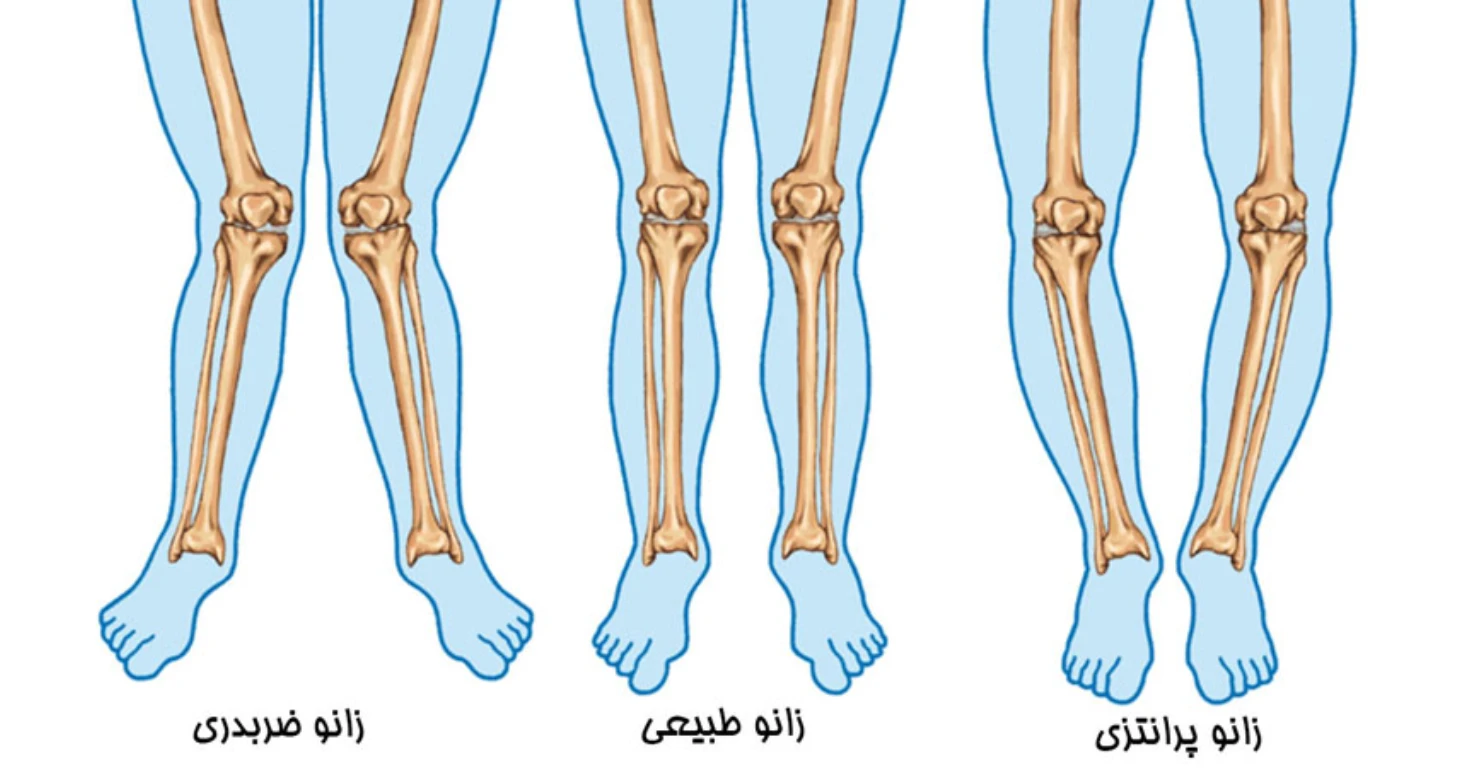

پای پرانتزی یک ناهنجاری در راستای طبیعی استخوانهای پا و زانو است که باعث میشود زمانی که مچ پاها کنار یکدیگر قرار میگیرند، زانوها به هم نرسند و بین آنها فاصله ایجاد شود. در حالت طبیعی، محور ران، زانو و مچ پا باید روی یک خط مستقیم قرار بگیرند؛ اما در فردی که پای پرانتزی دارد، این محور به سمت بیرون منحرف میشود و نتیجه آن تغییر در شیوه راه رفتن و ایستادن بدن است.

این ناهنجاری تنها یک مسئله ظاهری نیست، بلکه بهطور مستقیم روی عملکرد مفاصل و سلامت حرکتی بدن اثر میگذارد. زمانی که محور پا از حالت طبیعی خارج میشود، وزن بدن به جای آنکه بهطور یکنواخت در کف پا پخش شود، بیشتر روی لبهی خارجی پا و مفصل زانو متمرکز میگردد. این توزیع غیرطبیعی فشار، در طول زمان منجر به بروز مشکلات متعددی میشود؛ از جمله: